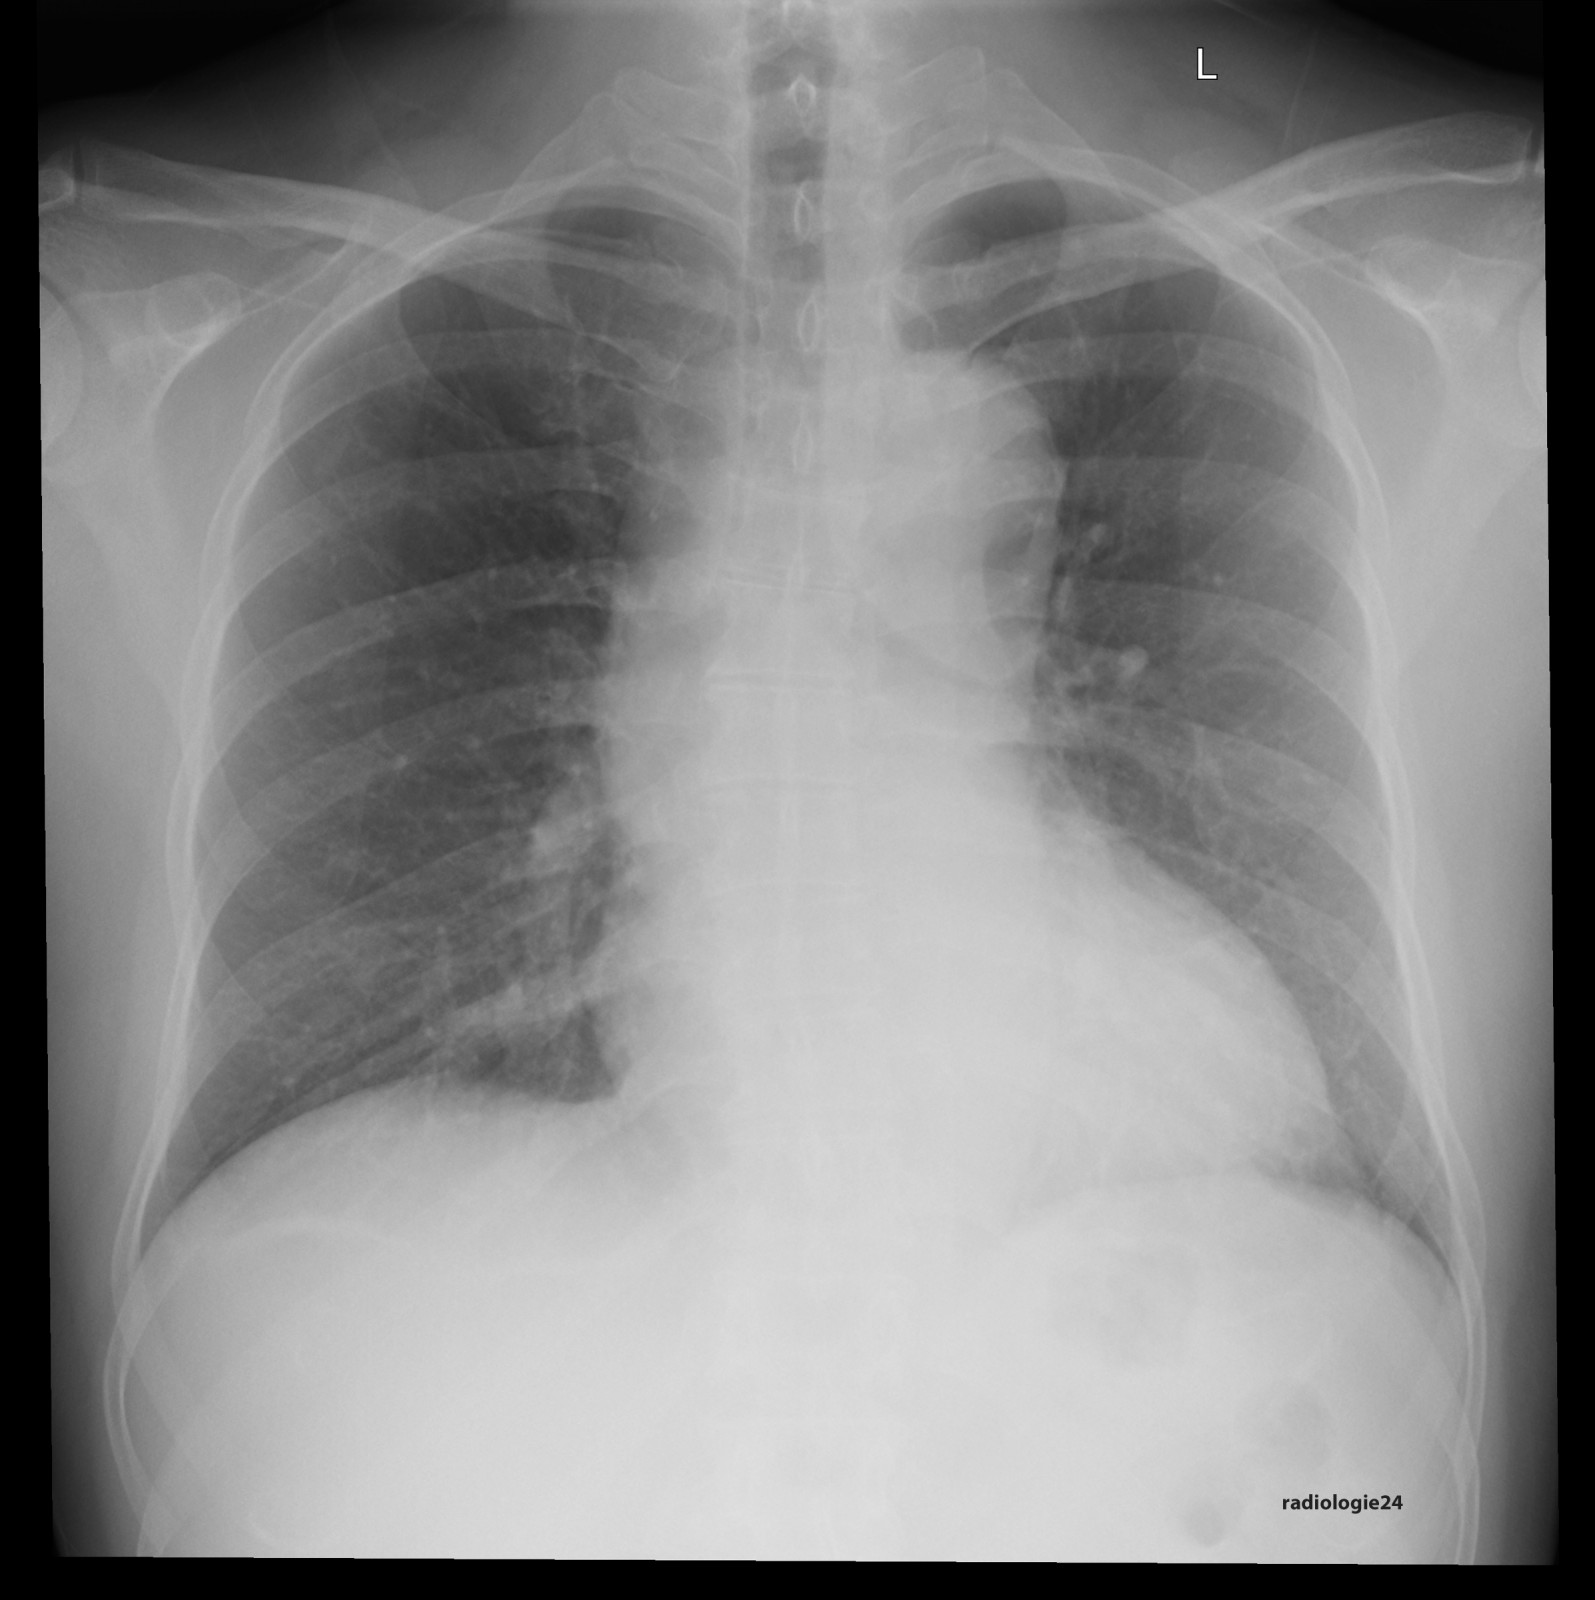

Link zur Auflösung mit ausführlichem Befund

https://www.radiologie24.ch/radiologie-mediathek/roentgenfall_des_monats